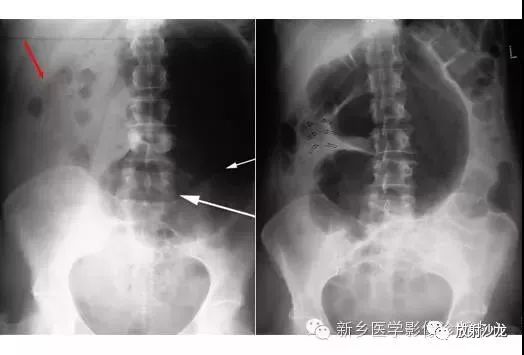

上图为一58岁男性,因1周前非特异性消化不良,行上消化道钡餐检查,做的腹部平片。患者最初表现为不确切的腹部不适和便血。现在又出现了腹痛和腹膜炎。箭头所指的典型表现是什么,诊断是什么?

箭头指向缺血穿孔性肠病患者的浅浮雕征。这也被称为双壁征或Rigler征。通常仅一侧肠壁可以看到。当双侧都能看到时,它表示腔内和腔外都有气体。当病人腹痛症状逐渐加重,肠壁穿孔是很有可能的。该患者手术过程中发现肠道脾曲缺血穿孔性肠病。